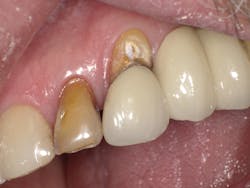

Case Three is a challenging crown repair on a medically compromised patient. The preoperative image shows decay at the buccal margin of an anterior abutment to a bridge (figure 11). Following excavation with the Lite Touch laser (figure 12), we decided to use Futurabond U in a self-etch technique followed by layering Admira Fusion in two increments. The first increment was an opaque layer, using shade OA2 to attempt to block out the gray margin of the porcelain-fused-to-metal crown (figure 13). After light-curing that layer, we applied shade A1 and light-cured and polished the restoration, achieving a highly esthetic result given the difficulty of the situation (figure 14).

Figure 11